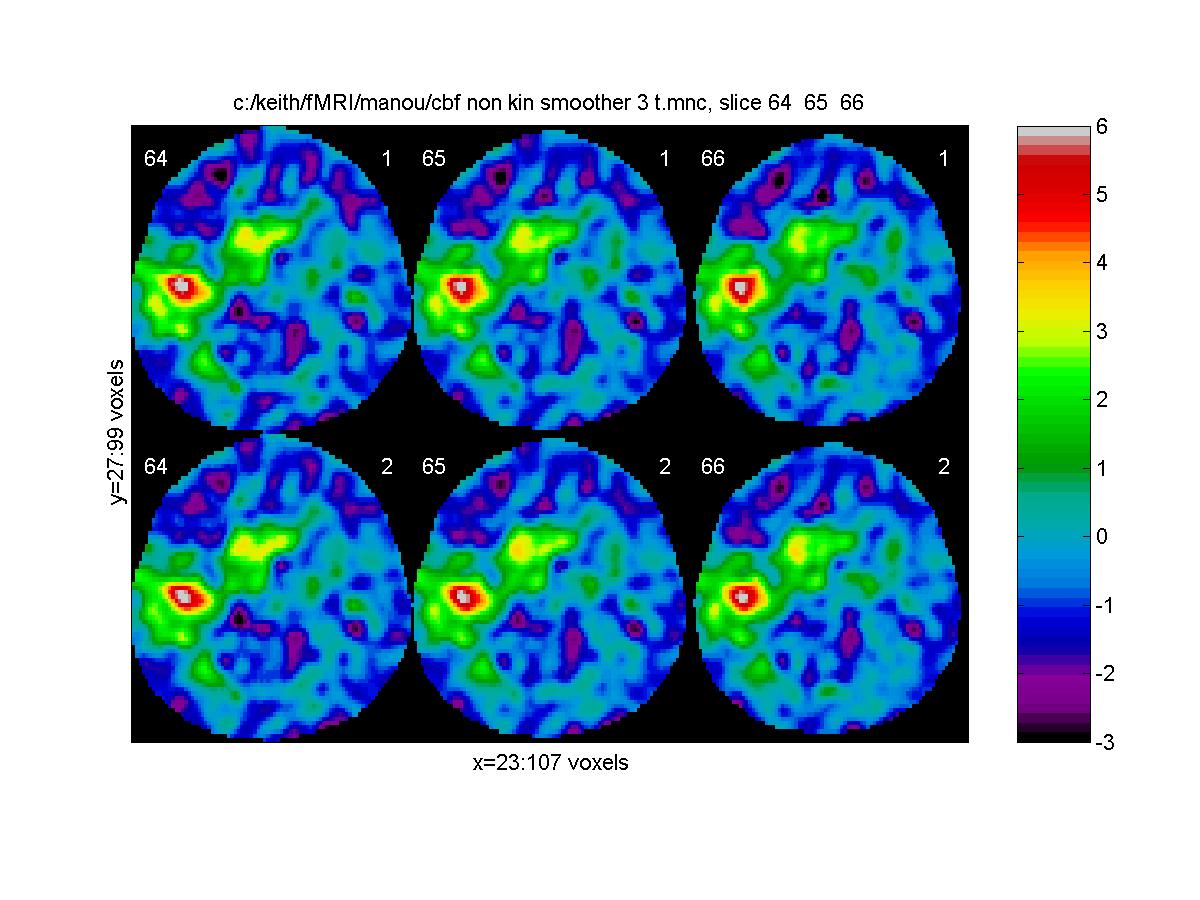

This time the sd is smoothed by fwhm_varatio = 11.2977mm to achieve 100 df. We can compare the two analyses as follows:

m=['c:/keith/fMRI/manou/cbf_non_kin_smoother_3_t.mnc';

'c:/keith/fMRI/manou/cbf_non_kin_smooth_3b_t.mnc ']

clf;

view_slices(m,mask,0.65,64:66,1:2,[-3 6],[1 2 3 4; 5 6 7 8])

![[Click to enlarge image]](figs_pet_tn/fignormt3b.jpg)

The top row is the first analysis (assuming independent scans with equal sd), the second row is the "safer" analysis which doesn't make this assumption. The difference is imperceptible in this case.